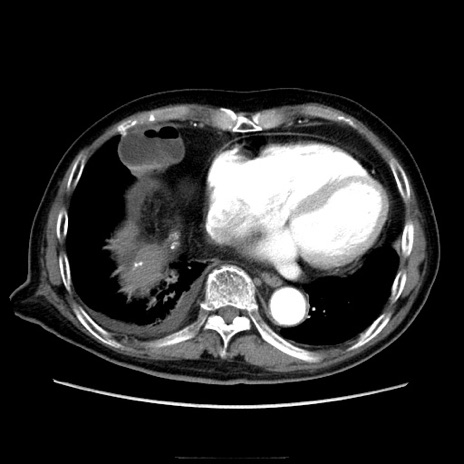

症例21(横断像)

【症例】70歳代男性

【主訴】腹痛

【現病歴】肝硬変・肝細胞癌にてかかりつけの方。約9時間前に食後より腹痛出現。症状が徐々に増悪し、嘔吐出現したため来院。

【既往歴】肝硬変、肝細胞癌(RFA、TACE後)

【身体所見】意識清明、表情苦悶様、BT 36℃、BP 129/78mmHg、P 88bpm、SpO2 97%(RA)、右上腹部から心窩部にかけて圧痛あり、反跳痛なし、筋性防御あり。

【データ】WBC 5800、CRP 0.16